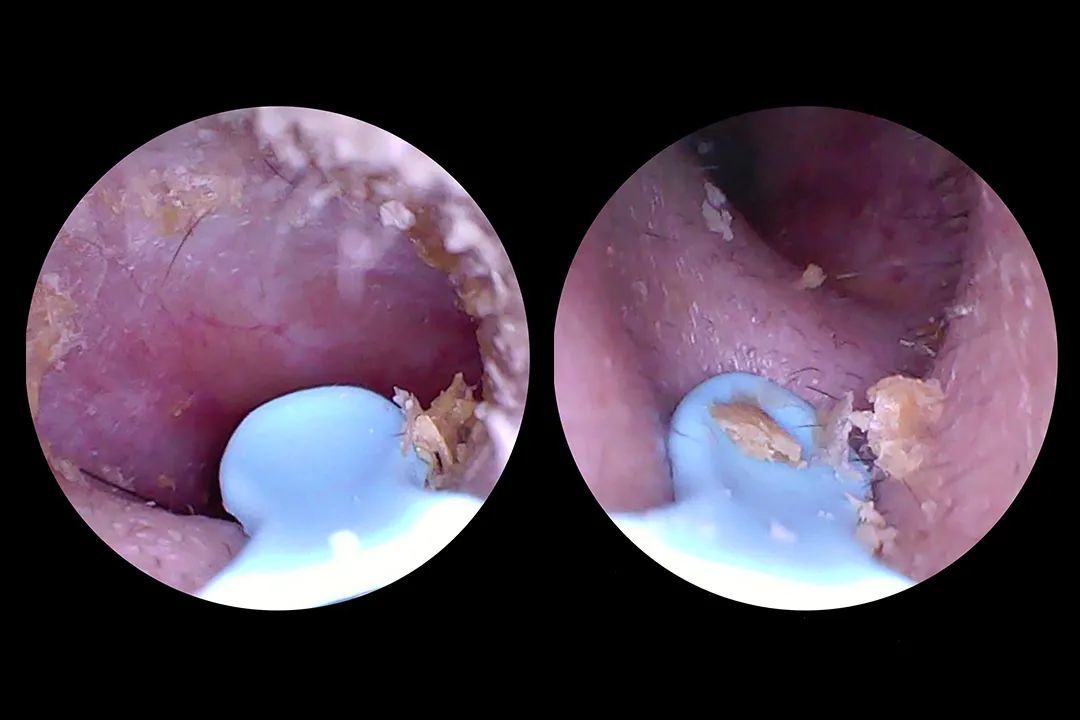

●第一次把耳勺伸进耳朵时,我仿佛打开了新世界:震撼画面:屏幕上赫然出现一片“金色沙漠”(耳垢)+“黑色灌木丛”(耳毛),甚至能看到耳膜若隐若现(友情提示:别戳它!)。

●精准打击:用耳勺头轻轻一刮,耳垢像雪崩一样哗啦啦掉下来;顽固分子换金属镊子一夹,爽感堪比挤黑头。

●1000万像素“千里眼”:医疗级微距镜头+纳米级内窥镜,耳垢、绒毛、皮肤纹理一览无余。实测连耳道里0.5mm的血管都能看清,恍惚间以为自己成了人体探险纪录片导演。